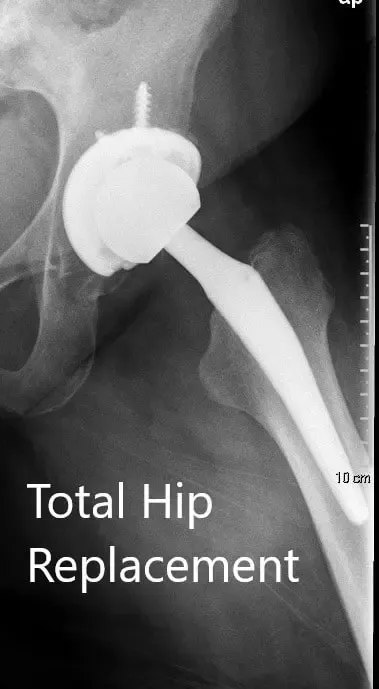

Radiografía postoperatoria que muestra la vista AP de la pelvis y la vista lateral de la cadera izquierda.

OPERACIÓN: Artroplastia total de cadera izquierda usando cabeza femoral cerámica de 36 mm más 5 con un sistema de tallo de cuello de 127 grados tamaño 5 con un agujero de racimo de concha acetabular de 54 mm con inserto de polietileno con dos tornillos.